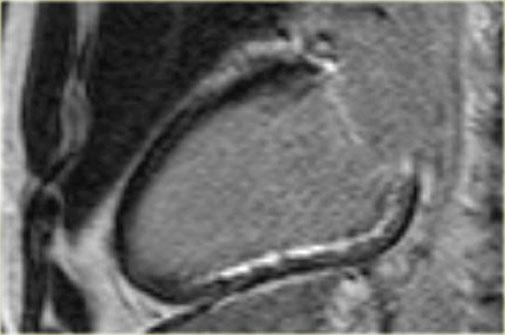

Bên trái là hình ảnh ngấm thuốc muộn góc nhìn 4 buồng và trục ngắn.

Có hình ảnh ngấm thuốc dưới nội tâm mạc toàn chu vi lan rộng vào cơ tim lân cận.

Hình ảnh ngấm thuốc muộn cho thấy sự ngấm thuốc trên toàn bộ chu vi dưới nội tâm mạc, lan rộng không đều vào cơ tim lân cận [21].

Đôi khi rất khó tìm được thời gian đảo ngược tối ưu để triệt tiêu tín hiệu cơ tim bình thường [1].